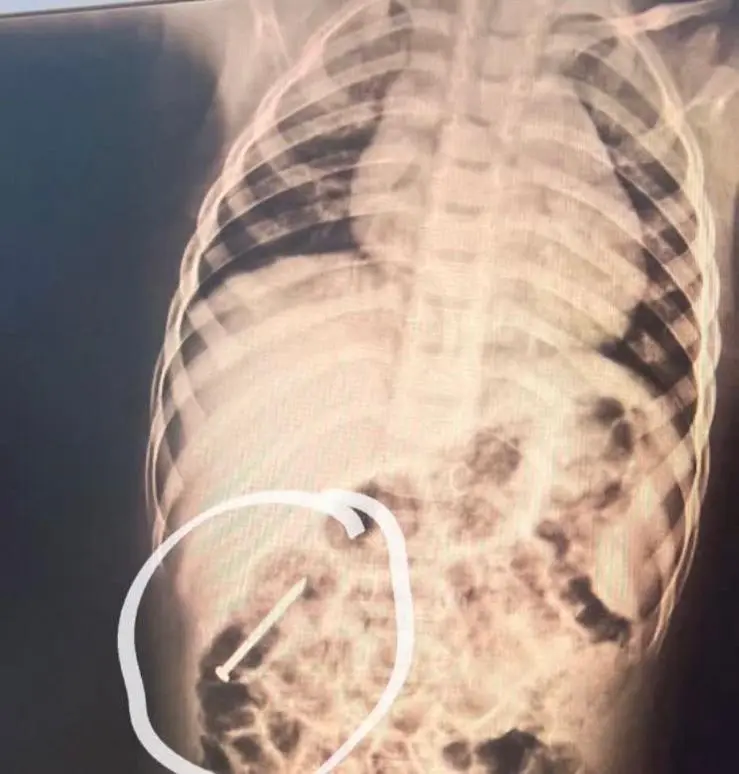

Menino de 3 anos está internado em Cruzeiro do Sul com prego alojado no intestino

Um menino de 3 anos está internado no Hospital do Juruá, em Cruzeiro do Sul, desde quarta-feira (14), após engolir um prego que ficou alojado no intestino. A criança, que mora em Ipixuna, no Amazonas, já havia engolido o objeto seis dias antes de ser transferida para o Acre.

O pediatra Rondney Brito atendeu a criança, que passou por exames e está sendo acompanhada também pelas equipes de endoscopia e cirurgia. A cirurgia só será realizada caso haja necessidade. Segundo o médico, o quadro da criança é estável e o prego deve ser expelido naturalmente pelas fezes.

“Acompanhamos a posição do prego diariamente com radiografias. Ele está se movimentando no sentido de saída do intestino. A equipe de cirurgia, incluindo o endoscopista Dr. Marlon Holanda, acompanha todo o caso. Como não há sinais de gravidade, estamos permitindo que o prego siga seu percurso natural pelo intestino. Caso haja qualquer alteração que exija cirurgia, ela será feita imediatamente. A criança está estável, comunicativa, se alimentando bem e sem sinais de gravidade”, explicou o pediatra, que se disse impressionado com o tamanho do prego.

“O que impressiona realmente é o tamanho do prego. Ele é grande, não é pequeno”, concluiu Rondney Brito.